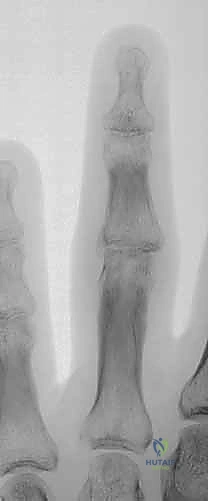

الحالة الأولى: كسر خلع ظهري مفتت بشدة

- قبل الجراحة: تظهر الأشعة خلعاً تاماً للمفصل مع تفتت شديد في قاعدة السلامية الوسطى.